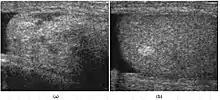

Doppler ultrasound of epididymitis, seen as a substantial increase in blood flow in the left epididymis (top image), while it is normal in the right (bottom image). The thickness of the epididymis (between yellow crosses) is only slightly increased (7 mm).

Doppler ultrasound of the scrotum of the same case, in the axial plane, showing orchitis (as part of epididymo-orchitis) as hypoechogenic and slightly heterogenic left testicular tissue (right in image), with an increased blood flow. There is also swelling of peritesticular tissue.